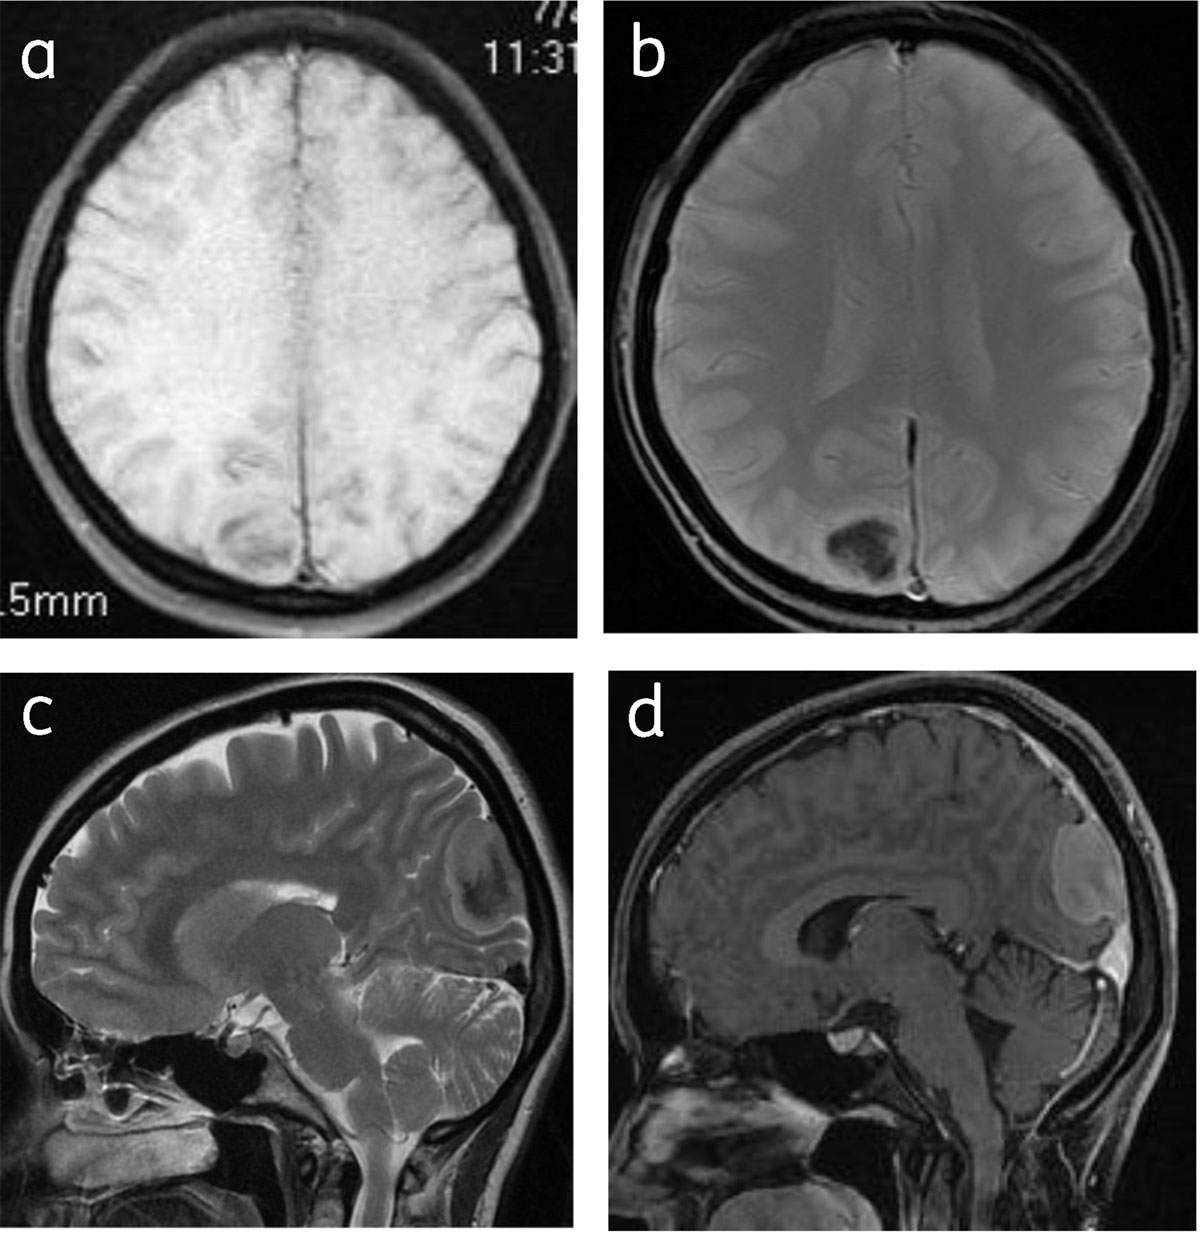

Approximately 25% show calcification [1] and appear hypointense on T1 and T2WI, with blooming on GRE (Figure 3).

Figure 3

Calcified meningioma: Axial T1WI (a), T2* gradient (b), sagittal T2W (c) and sagittal post contrast (d) images shows right parafalcine calcified meningioma with hypointense central signal.